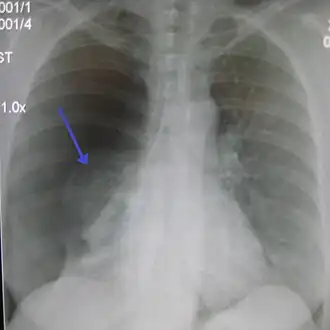

La radiographie du thorax de face permet de faire, en règle générale, le diagnostic, sous forme d'une clarté d'un sommet (ou péri hilaire dans les cas plus important) avec visualisation d'un fin liseré convexe vers le haut, correspondant au poumon rétracté. Dans les cas difficiles, on peut s'aider d'une radiographie prise en expiration. La présence simultanée d'un épanchement liquidien donne l'aspect de niveau hydro-aérique rectiligne horizontal caractéristique.